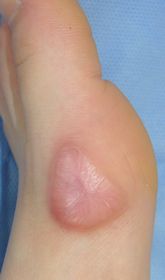

7歳男。

受賞後,しばらく歩こうとせずに松葉杖で歩いていたが,11月10日,突然走りだした。

| 10月27日 | 10月29日 | 11月6日:10日後 | 11月13日:17日後 |